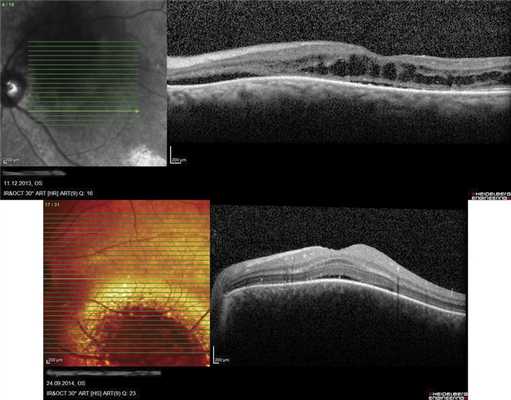

ОНЭ с отеком и дезорганизацией дисков наружных фоторецепторов в макулярной зоне выявлена у 12 больных с ГХ со снижением зрения до 0,02-0,8, проминенцией опухоли 1-4,05 мм и анамнезом заболевания от 1 мес до 15 лет. Наиболее выраженное снижение зрения (до сотых) отмечали в случаях пара- и макулярного расположения ГХ и длительности анамнеза более 10 лет (рис. 5, а), минимальное снижение остроты зрения (до 0,6-0,8) - при длительности анамнеза до 1 года (см. рис. 5, б).

Рис. 5. ОКТ-горизонтальный срез через макулярную зону. а - пациентки Е., Vis OS =0,02, длительность анамнеза 11 лет (ОНЭ, кистозные изменения в макулярной зоне с разрушением фоторецепторов); б - пациентки С., Vis OS =0,7-0,8, длительность анамнеза 6 мес (отечность наружных сегментов фоторецепторов).

В 8 случаях выявили распространенную зону ОНЭ с дезорганизацией фоторецепторного слоя «на протяжении» от очага (рис. 6, а). В 2 случаях при анамнезе более 15 лет были выявлены зоны разрушения слоя фоторецепторов и наружных слоев сетчатки, соответствующие зонам ранее существовавшей ОНЭ (см. рис. 6, б).

Рис. 6. ОКТ-горизонтальный срез «на протяжении» от ГХ. а - пациентки Х., длительность анамнеза 3,5 года (красными стрелками указана зона ОНЭ); б - пациентки К., длительность анамнеза 15 лет (желтыми стрелками указана зона разрушения слоя фоторецепторов и наружных слоев сетчатки на месте ранее существовавшей ОНЭ, атрофия РПЭ).

Следует отметить, что появившиеся морфофункциональные изменения в сетчатке при ГХ прогрессируют крайне медленно, что мы имели возможность подтвердить у 8 больных при повторных ОКТ с интервалами от 3 до 25 мес. Этот факт важен при планировании лечения больных с достаточно хорошим зрительным прогнозом. Ранние изменения в сенсорной части сетчатки (при анамнезе 3 мес) находили и другие авторы [10].

Оценивая ОКТ-симптоматику ГХ, можно сказать, что нарушение архитектоники сетчатки, в том числе ее кистозная дистрофия, возникают при проминенции опухоли более 1,8 мм, а отек сетчатки - чаще при ее бо́льшей толщине [15]. В то же время имеются сведения, что куполообразная элевация хориоидеи с фокальной гиперплазией надлежащего РПЭ может сочетаться с серозной отслойкой сетчатки над опухолью и сохранной архитектоникой сетчатки, нормальным слоем фоторецепторов и отсутствием интраретинального отека [9, 16], что расценивают как отражение остроты процесса [6].